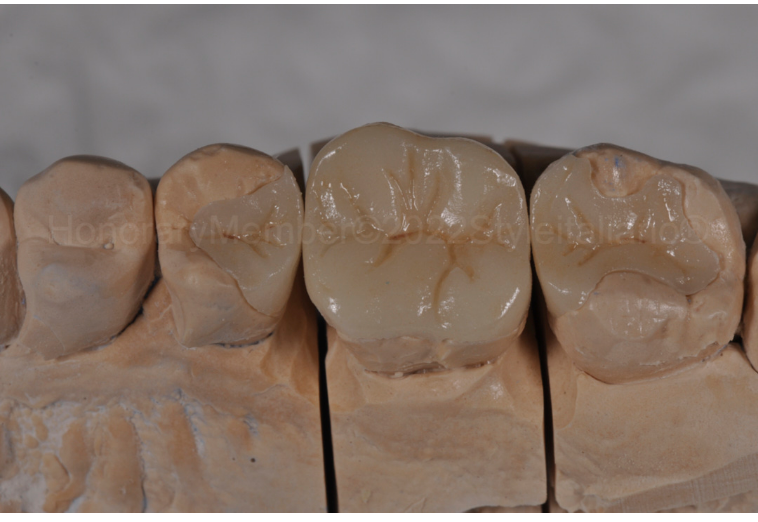

图七:为了给嵌体修复提供所需的厚度,进行了嵌体修复的预备。深的龈壁边缘不再存在。由于牙本质替代物,我们将龈壁边缘提高到龈上水平,以精确所有即将到来的临床步骤(印模、临时和粘接方案)。

图八:印模制取。

图九:全瓷嵌体。